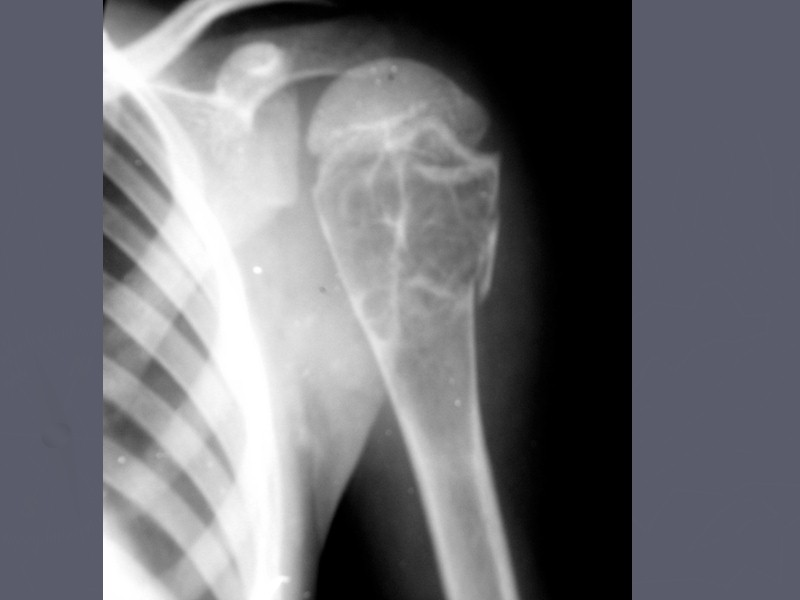

Хондробластома (опухоль Кодмана) До 2% от всех доброкачественных костных опухолей Выявляется в возрасте от 10 до 25 лет, в 2 раза чаще у мужчин Одиночная Преимущественная локализация – эпиметафиз длинных трубчатых костей Излюбленная локализация проксимальный эпиметафиз плечевой кости (опухоль Кодмена), не встречается в черепе является типом опухоли, переходным от хрящевой к остеогенной Может вызывать легкое вздутие кортикального слоя Не малигнизируется

Рентгенологические симптомы Выглядит как эксцентрично расположенный очаг просветления (хрящевая ткань), с вкраплениями костного вещества, с четким склеротическим контуром. Иногда прослеживаются линейные периостальные наслоения, которые быстро ассимилируются.